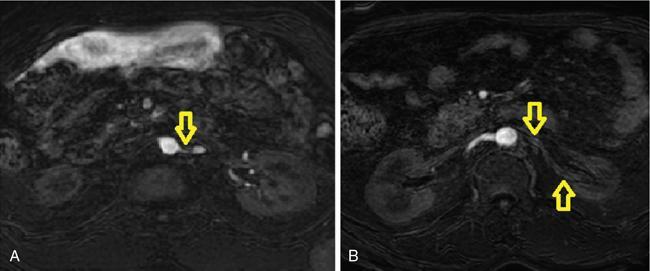

• MRA: It is useful in patients with contraindications for intravenous iodinated contrast and in patients with elevated serum creatinine. MRA findings in RAS are similar to those in CTA. Noncontrast MRA can detect RAS in main renal arteries with limited evaluation of segmental and intrarenal branches (Fig. 10.18.1.6A and B). Contrast-enhanced MRA helps in better delineation of entire renal arterial tree. Sensitivity and specificity of noncontrast and contrast-enhanced MRA are 94% and 85% and 97% and 93%, respectively.

Fig. 10.18.1.6 Noncontrast MR angiography showing severe stenosis of ostioproximal left renal artery [arrow in (A)] and another patient showing loss of signal in left renal artery [arrows in (B)], suggesting total occlusion. (Source: Courtesy of Dr. Sreenath Sethumadhavan.)